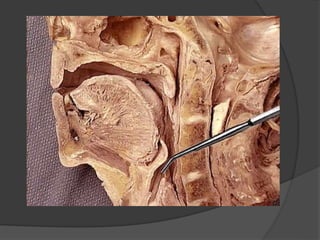

Palatine Tonsil

- Almond shaped Lymphoid tissue in Lateral wall of oro-

pharynx in tonsillar sinus

- Boundaries of tonsillar sinus

Front – palato glossal sinus

Behind – Palato glossal arch

Apex – Soft palate

Base – Post 1/3rd of tongue

Lateral wall – Tonsillar bed

Parts : 2 surfaces – Medial & Lateral

2 Ends – Upper & Lower

2 borders – Anterior & Posterior

Medial Surface

- Free, bulges into oro pharynx

- Lined by NKSSE

- Tonsillar pits – 12 th 15 in numbers

- Intra tonsillar cleft / crypta megna 40% remanant of IInd pharyngeal

pouch

- Embryonic folds – Plica semilunaris

-- Plica tringularis